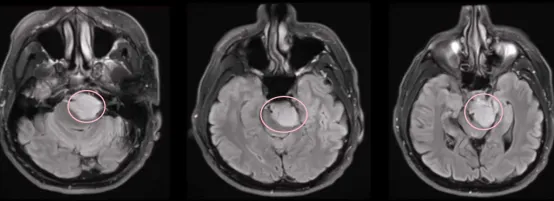

针对这种情况,患者MR检查明确巨大岩斜区脑膜瘤,手术治疗难度大:

1.位置“深藏不露”,岩斜区这个神秘的地带,藏身于我们头骨的深处,就在颞骨岩部和枕骨斜坡的交汇处,从岩骨尖一直延伸到颈静脉孔。

2.不可得罪的“VIP”邻居:它外侧挨着第Ⅴ、Ⅶ和Ⅷ脑神经,内侧则朝着斜坡的中线,顶上是鞍背,底下是颈静脉孔水平线,下面还紧邻着枕骨大孔区。这个区域深不可测,周围都是些身体里的“VIP”结构。想要彻底切除肿瘤?难度系数五颗星!而且术后可能会有点小麻烦,致残风险,一直是神经外科医生们头疼的治疗难题。

术后CT未显示任何术后并发症,术后MRI显示脑膜瘤几乎完全切除。